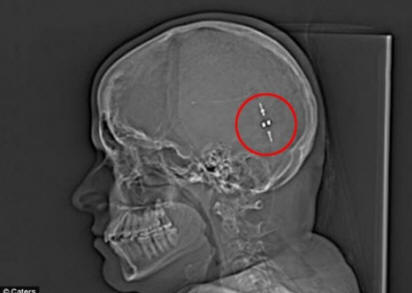

Toda potem, ko so našli način, kako odstraniti odvečno tekočino iz možgani v trebuh, njeno življenje se je spremenilo. Odtok, znan tudi kot gastroperitonealni shunt, povezal možgane in želodec, kar je omogočil prebavi možgansko tekočino in zmanjša pritisk na možgane.